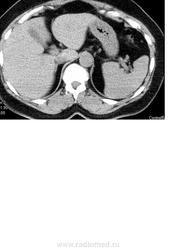

Добрый день! помогите пожалуста описать исследование. Пациентка 51 г.р., по УЗИ гипоэхогенное образование в левой доли печени 3х3,5 см с четким, неровным контуром.

Кистозное образование(?) размерами.., плотностью.. едН, расположено там то. Я думаю, что это киста.

Не надо делать КТ печени без контраста, не информативно это.